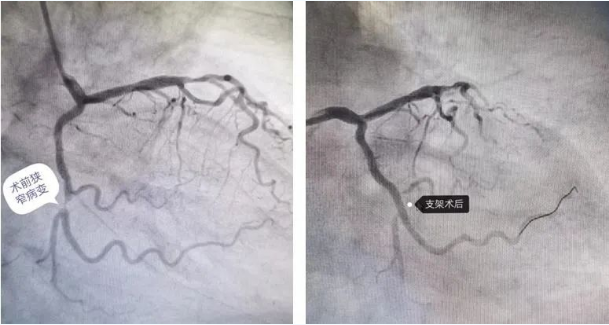

前几天,80岁的徐老先生夜间休息时突然出现左侧胸痛症状,呈闷痛,向后背部放射痛,伴有出汗、左上肢麻木等不适,家人急忙将老人送到蜜桃视频-麻豆蜜桃 心内二科就诊,经检查明确诊断为急性心肌梗死,紧急行冠脉介入治疗。冠状动脉造影术检查显示回旋支近段可见散在斑块,中段可见局限性狭窄,狭窄最重约99%,远端未见明显狭窄,左主干、前降支及右冠未见明显狭窄,经评估后,顺利为老人行经皮冠状动脉支架植入术。

术前、术后病变血管变化

由于救治及时,术后徐老先生胸痛症状消失,两日后可自主活动,日常生活自理。